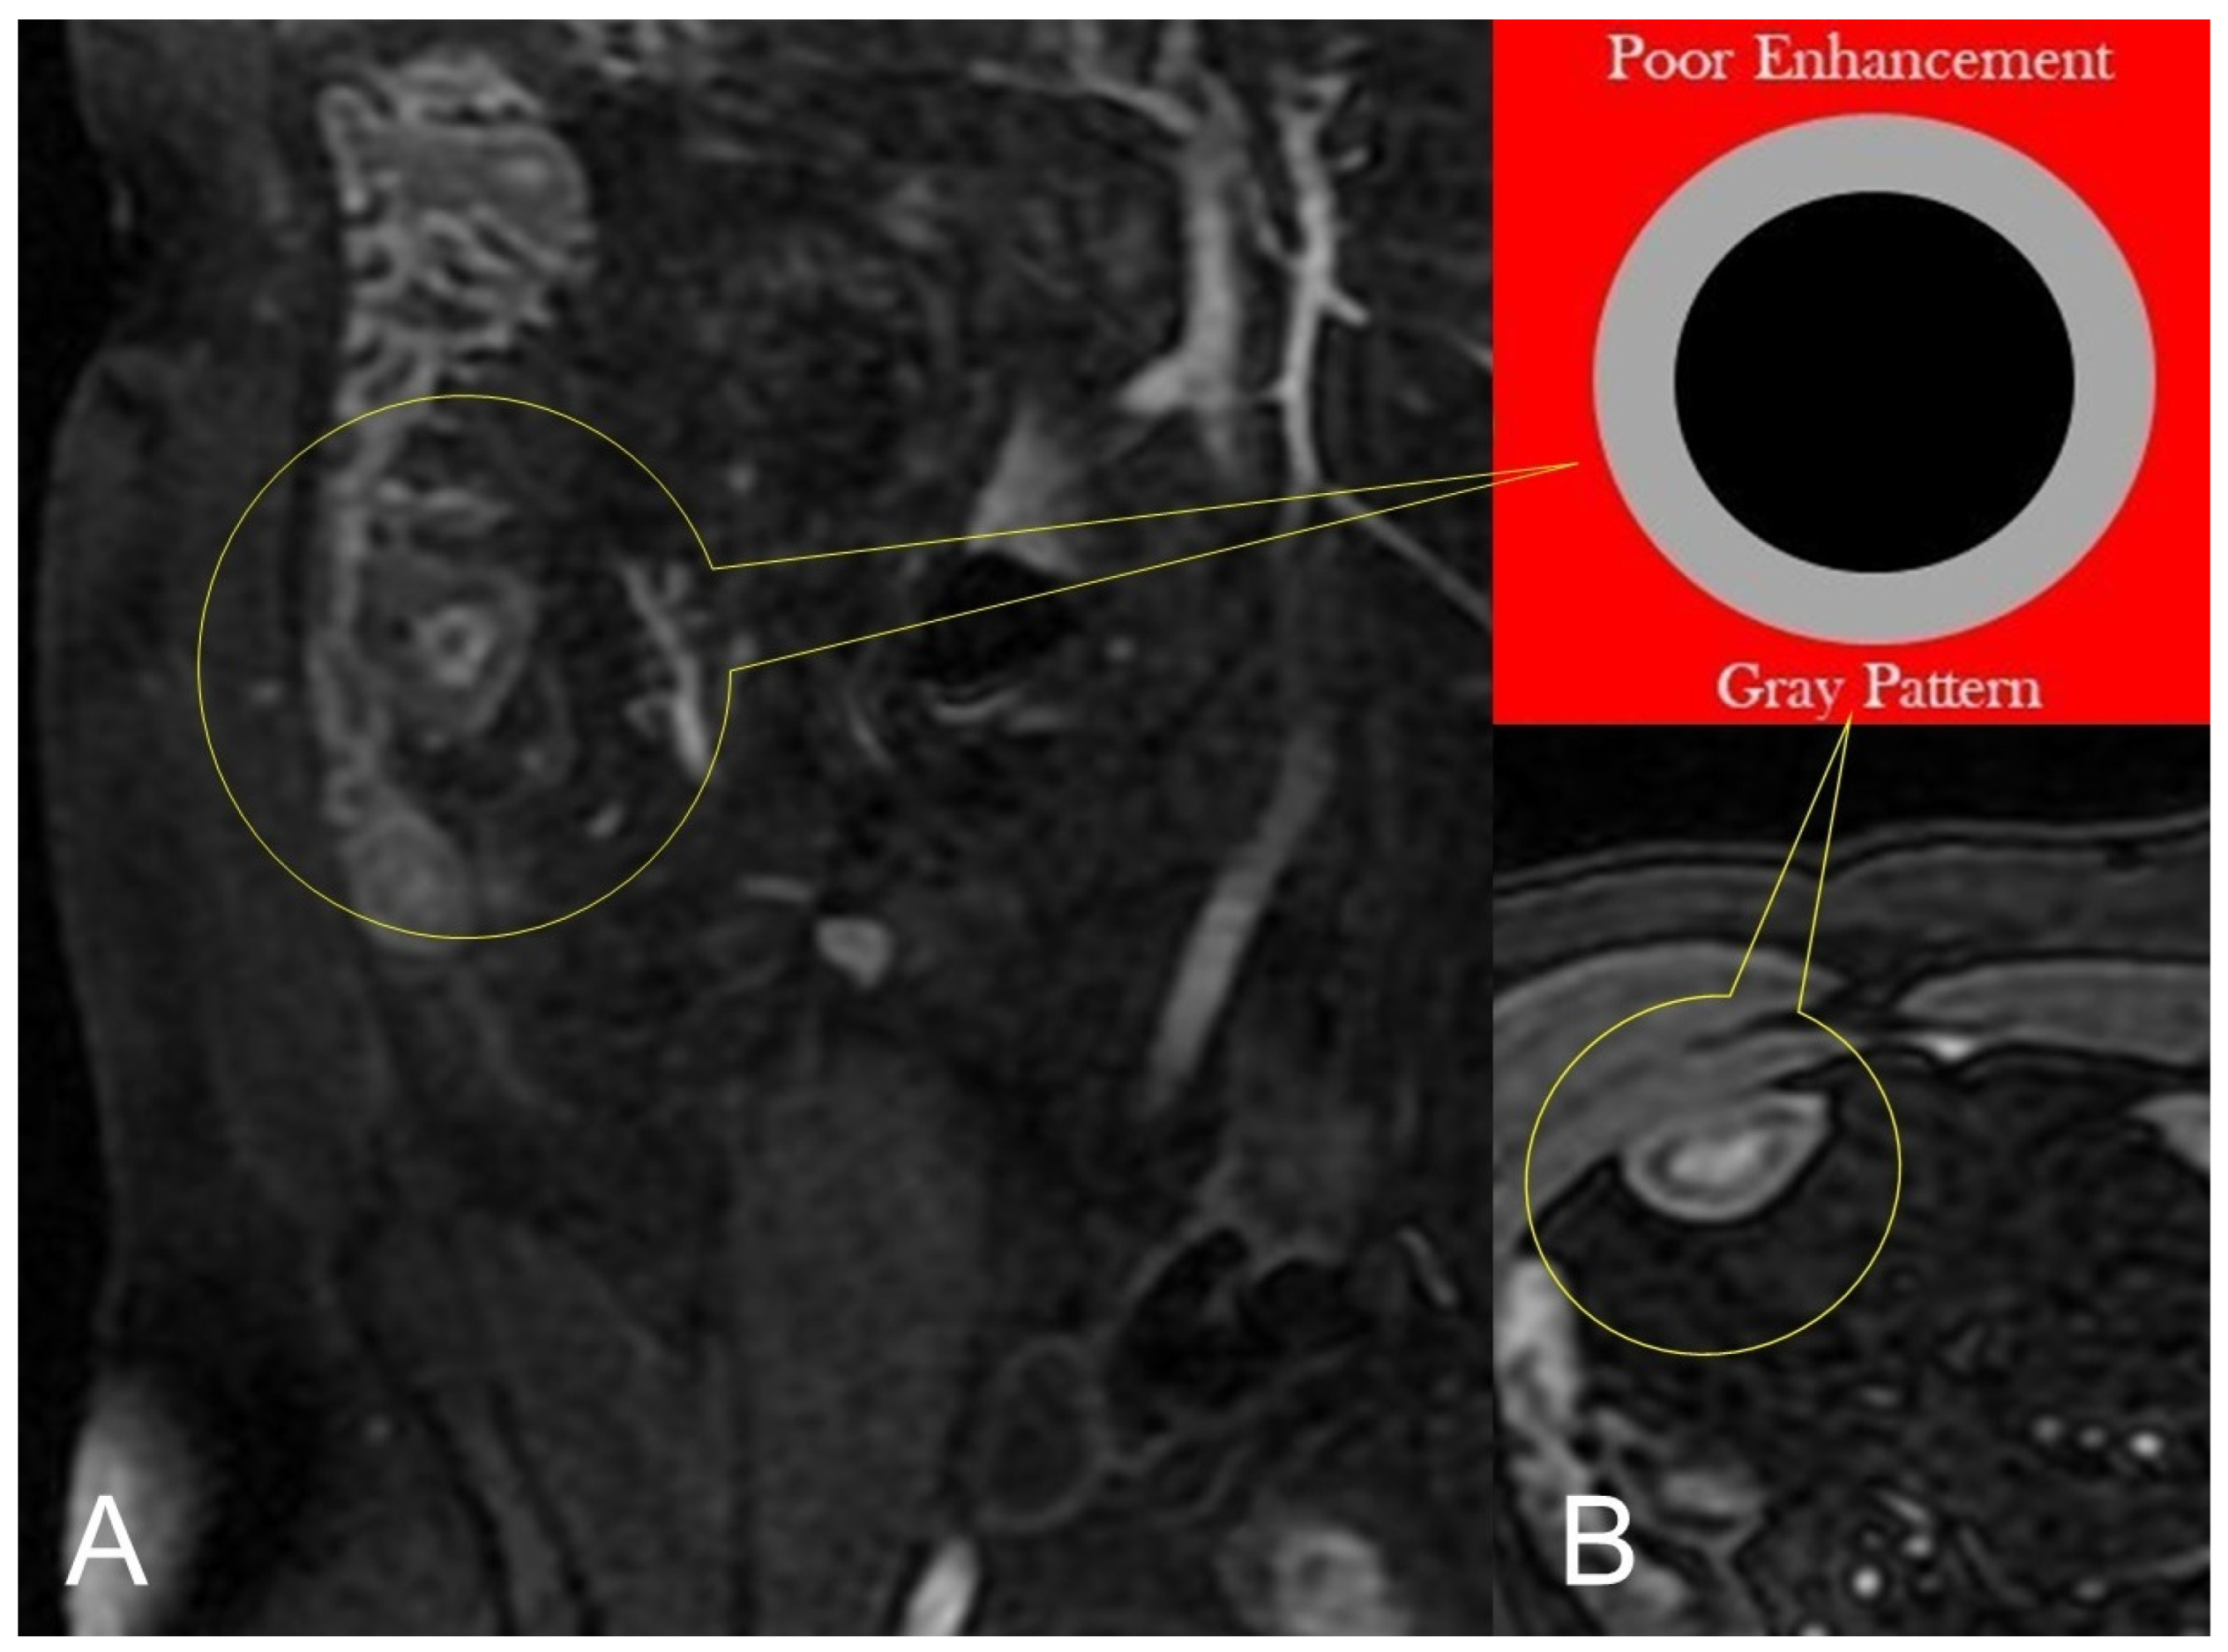

Figure 4.

Lack of layered or homogeneous enhancement can be related to fat ((B), axial FIESTA) image, or fibrosis parietal deposition, with poor enhancement and gray pattern on contrast-enhanced fat-suppressed T1-weighted image ((A), coronal image).

In chronic disease, there is a fat deposition in the submucosal layer that appears as hypo-intensity in the thickness of the intestinal wall on T2-weighted images with fat saturation (Figure 4B).

During subacute transmural inflammation, the thickened and fibrotic bowel wall exhibits diffuse and homogeneous contrast enhancement, and the mild mucosal enhancement with hypo-intensity of the deep layers suggests fibrotic condition [19].